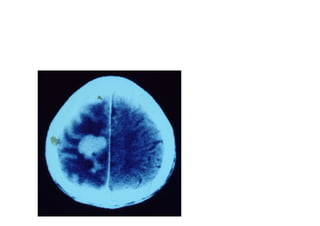

Vascular

Hemorragica

Isquemica

Neoplasica